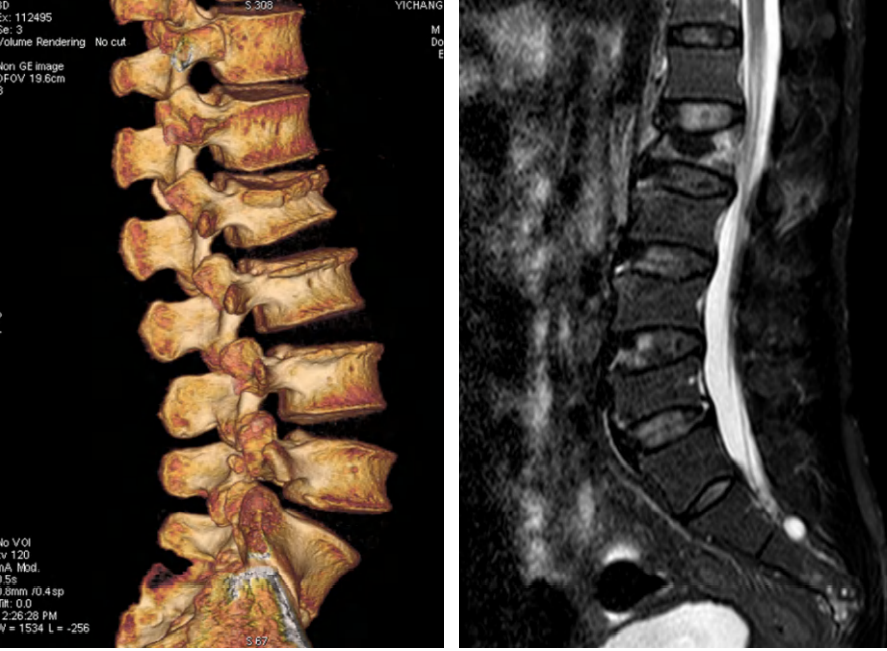

病例2车祸伤,完全性脊髓损伤

AO分型

- 分型:T12L1 C型;T12 B2型,L1 A1型

- 神经功能障碍分级:N4

- 修正参数:

- AO补充评分:C+N3(8+4) 12分

TLICS评分

- 骨折脱位(3分)

- 完全性神经损伤 (2分)

- PLC断裂(3分)

- 8分

载荷评分

- 碎裂大于60% 3分

- 后凸4~9度 2分

- 移位大于50% 3分

- 8分,合并脱位

治疗方案:手术治疗;后路手术,长节段固定